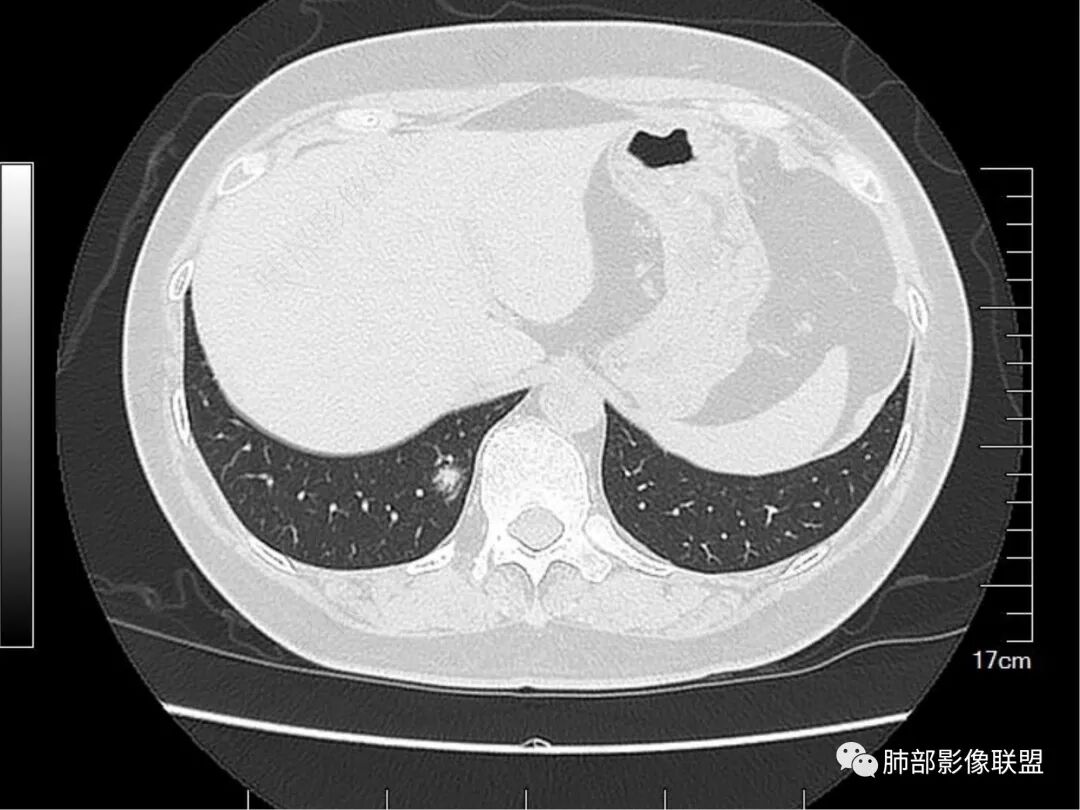

老年女性,右肺多发结节,形态不规则,有一定的收缩,内可见支气管影,周围可见边缘模糊的磨玻璃及长毛刺,考虑炎性病变,隐球菌感染可能。

老年人,右肺上叶后段小结节影,边缘清楚,血管进入,内可见支气管穿行扩张,周围晕征,边界清楚,胸膜牵拉,考虑腺癌。

老年女性,右肺多发结节,形态不规则,有一定的收缩,内可见支气管影,周围可见边缘模糊的磨玻璃及长毛刺,考虑炎性病变。

右上肺膜玻璃影,边界清楚,临近胸膜牵拉,考虑腺癌,右下肺病灶考虑炎症。

右肺上叶后段及下叶后基底段混合磨玻璃结节,界不清,内似见扩张支气管,一年间有增大,考虑腺癌可能性,建议抗炎半月后复查

右肺上叶后段病灶考虑腺癌,右肺下叶后基底段病灶考虑粘液性腺癌,上叶病灶GGO清晰,收缩力强 下叶的病灶GGO模糊不清、收缩力弱

右肺上丶下叶病灶考虑同性质,混合磨玻璃结节,很多地方不太支持恶性(腺癌),比如扩张支气管可以在结节周边,以下叶的结节明显,磨玻璃边界欠清!综合考虑良性结节,支气管畸形结节可能!

就是没看到复查片总不踏实。这个结节的特点有些怪,连续的层面显示内部、边缘就是一张网格,走形非常自然,这些图,你看到的GGN边缘就不踏实,这是GGN边缘?还是就是增厚的间质

老年女性,体检发现、一年“稍增大”,右上肺结节(扩张小支气管或空泡+收缩力明显),考虑腺癌(腺泡为主),右下肺结节(边缘模糊GGO+扩张小支气管),考虑肉芽肿性炎(隐?),一元论:MALT不考虑(右上肺病灶收缩力太明显)

右肺上叶后段及下叶后基底段亚实性结节,边界清楚,不规则,支气管血管破坏,结节见小空泡感,老年女性,复查拟有所增大,支持恶性,IAC。

右肺多发磨玻璃结节,上叶结节可见分叶及空泡,结节内血管穿行,血管影粗细不均,结节内支气管扭曲,定性恶性,下叶者结节较散,边界不清,综合分析支持多原发微浸润性腺癌,实际工作中右上结节为主病灶,诊断恶性依据充足,右下病灶建议抗炎后复查更稳妥